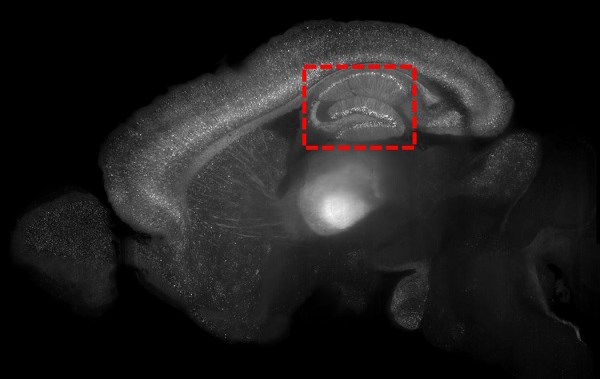

Dr. Paul Frankland, Senior Scientist in Neurosciences & Mental Health at the SickKids Research Institute, and his team trained infant mice to associate a specific place with a particular memory. This training engages the hippocampus, which plays a role in processing memories tied to a particular situation or context. The resulting memory of the place was forgotten within approximately one week.

Next, they conducted the training again with different mice but this time they identified and tagged the specific neurons that were active in the hippocampus to keep track of them for the next phase of the study. Weeks later, when the place had long been forgotten, the researchers stimulated the tagged clusters and found the mice behaved as if they recognized the place once again.

The team used a precise method called optogenetics to selectively stimulate the clusters of neurons that corresponded with the infantile memory. When the researchers tagged the relevant clusters of neurons during training, they inserted a gene to make them responsive to light. Then, the researchers activated the tagged neurons by delivering light into the brain.

“The optogenetic strategy we used was crucial to achieve the level of precision needed to test whether we could bring these memories back,” explains Frankland. “We were able to target specific clusters of neurons for specific periods of time to recreate very specific memories.”